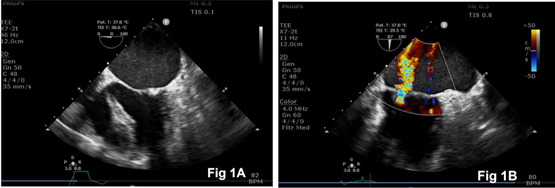

A 48-year-old man presented with worsening dyspnea and palpitations and was admitted for evaluation. Transthoracic echocardiography indicated severe mitral stenosis, moderate mitral regurgitation, and mild tricuspid regurgitation. The patient underwent mitral valve replacement surgery. After the induction of general anesthesia, a transesophageal echocardiography (TEE) probe was inserted, confirming the preoperative findings (Fig.1). The right internal jugular vein was cannulated for the insertion of an introducer sheath and PAC by a skilled anesthesiologist. The integrity of all ports and the inflation and deflation of the PAC balloon (Edwards Lifesciences LLC, CA, Irvine, USA) were confirmed before insertion (Fig. 2A, 2B).

Figure 1: Intraoperative transesophageal echocardiography images showing mitral stenosis (Fig. 1A) and mitral regurgitation (Fig. 1B).